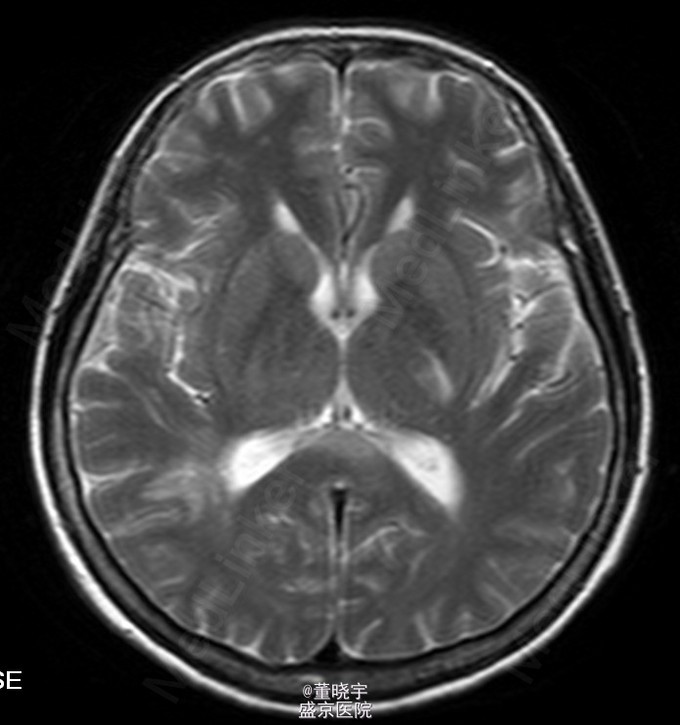

神经系统专科查体:神清语明,双瞳等大正圆,D=4.0mm,对光反射迟钝,视力丧失,双眼球各向运动充分,无复视及眼震,额纹对称,双侧鼻唇沟对称,伸舌居中,转颈有力,四肢肌力Ⅴ级,肌张力正常,双上肢指鼻准确,双下肢跟膝胫试验稳准,BCR L++R++, TCRL++R++,PSRL++R++,Babinski征L+R+,Hoffmann征L-R-,颈强,双掌颏反射(+)。 辅助检查:腰穿压力200mmH2O,细胞总数28*10^6/L,白细胞24*10^6/L,氯化物118.0mmol/L,糖2.41mmol/L,蛋白2.1g/L。 视觉诱发电位:双侧视通路传导障碍。 颅脑MRI见上。 核抗体(ANA)阳性;抗SS-A及抗SS-B抗体均阳性;IgG、IgA升高;补体 C3、C4下降。

诊断:原发性干燥综合征合并中枢损害 处理:静脉点滴丙种球蛋白治疗,临床症状稳定后出院口服强的松片10毫克/天。

半年后患者再次入院复诊,复查颅脑MRI提示新增病灶,但风免相关化验未见改变,急性长期口服激素治疗。 讨论:原发性干燥综合症(pSS)是一种以唾液腺和泪腺腺体淋巴细胞浸润和破坏为特点的自身免疫性疾病,临床主要表现为眼干、口干。腺体外表现主要是由于类似的单核细胞浸润或血管炎引起。CNS-SS的发病率及其颅脑MRI表现目前仍存在争议,有文献报道CNS病变发生率为0%-60%[1]。既往的一个400例患者大样本研究发现,只有1%患者合并CNS并发症。 CNS-SS的临床表现多样,脑部病变包括局灶性和弥漫性病变,局灶性病变主要表现为局部感觉和运动异常、失语、癫痈发作、构音障碍和视觉减退等;弥漫性病变主要表现为亚急性或急性脑病、无菌性脑膜脑炎、心理障碍和认知障碍等。中枢神经系统病变多隐匿起病,少部分患者呈急性或亚急性起病,部分患者同时合并有周围神经系统损害,加上部分pSS患者以中枢神经系统损害为首发症状,使得临床症状表现多样,诊断困难,极易误诊、漏诊并延误治疗。 目前对于pSS合并中枢神经系统病变治疗还没有统一的方案,大剂量激素治疗是目前临床中常用的方法之一,也有报道对于激素效果不佳的患者合并应用环磷酰胺也收到了不错的效果。静脉注射丙种球蛋白(IVIg)也是免疫相关的中枢神经系统病变常用治疗手段之一,尽管外文报道IVIg对于pSS引起的周围神经病变效果明显。